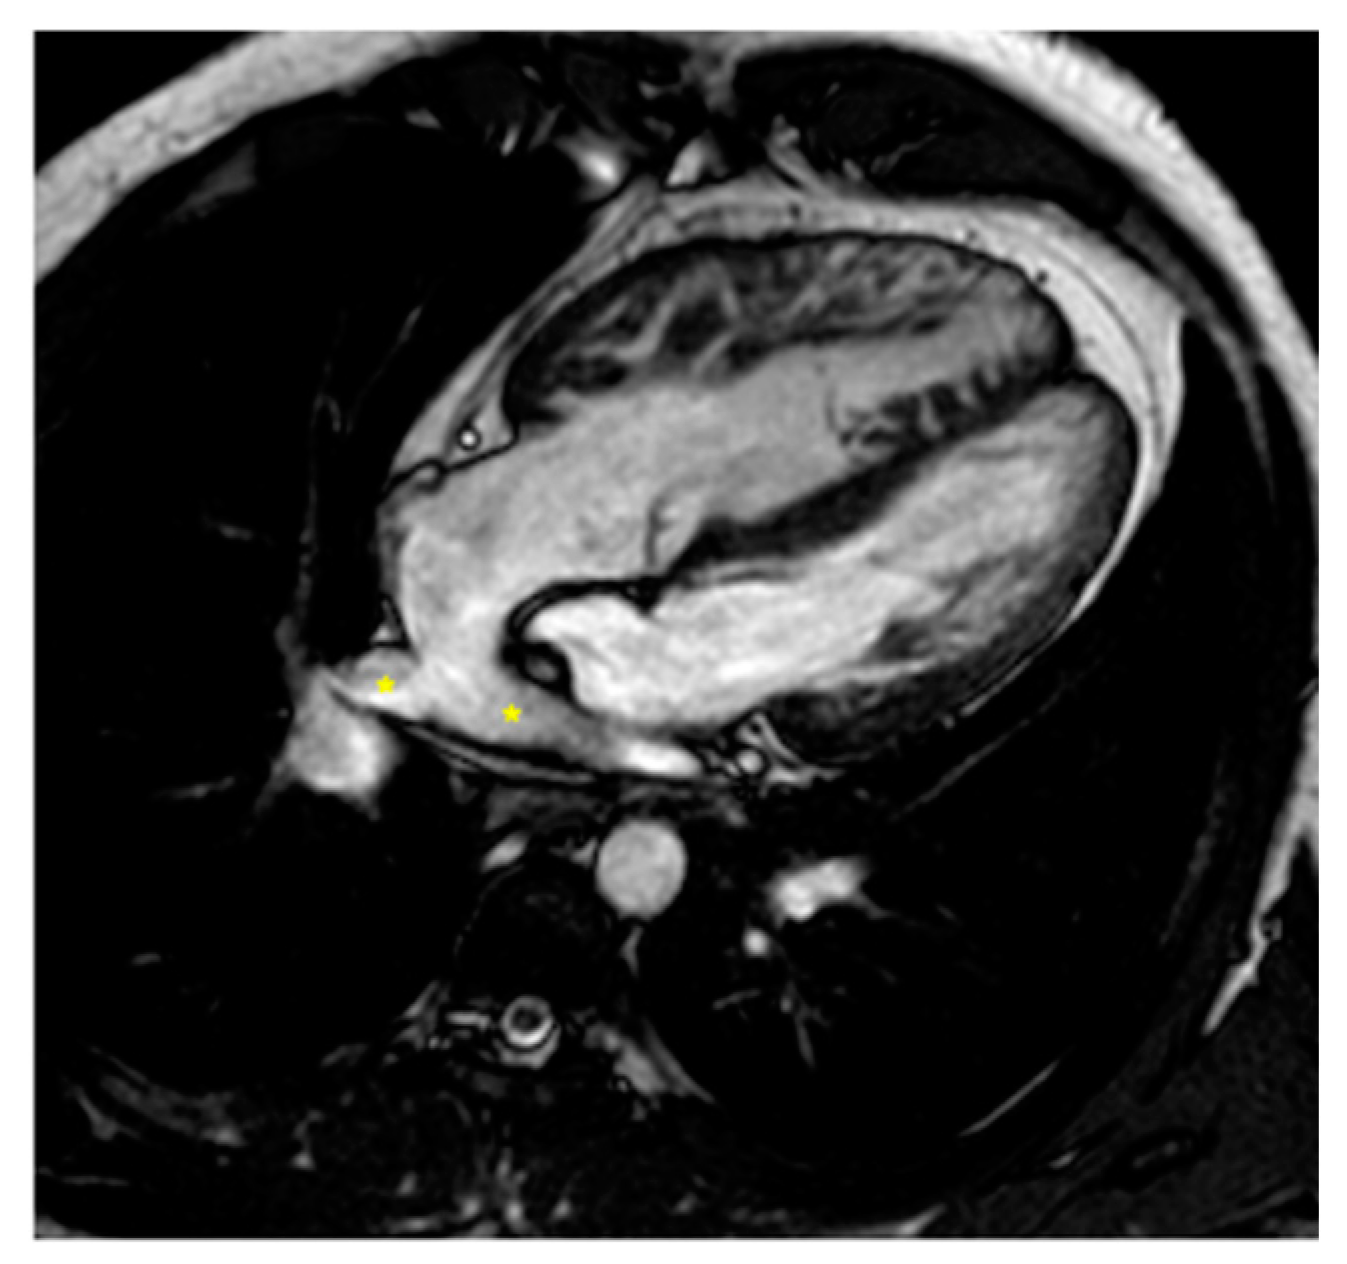

2.3. Coarctation of the Aorta